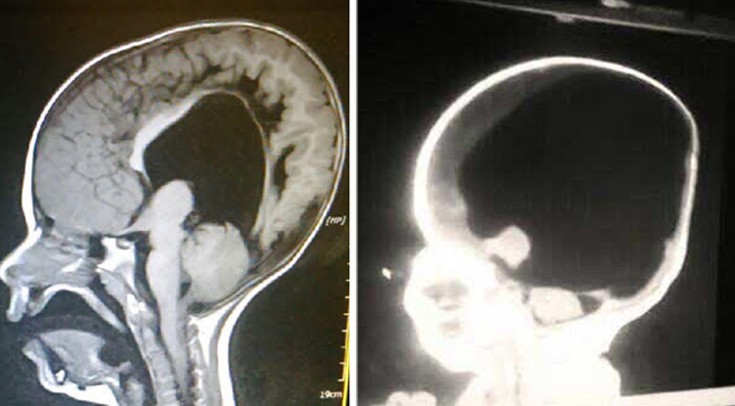

Ο μικρός Noah Wall άφησε κατάπληκτους όλους τους γιατρούς που δεν πίστευαν ότι θα επιβίωνε κατά τη γέννησή του καθώς ο ίδιος είχε μόλις 2% της λειτουργίας του εγκεφάλου του. Τώρα, όμως, το μυαλό του μικρού έχει αναπτυχθεί και εξελιχθεί σχεδόν όσο ενός μέσου τετράχρονου. Αψηφώντας, λοιπόν, όλες τις προβλέψεις το αγοράκι από φέτος πηγαίνει κανονικά στο νηπιαγωγείο ενώ οι γονείς του πίστευαν ότι δεν θα καταφέρει να ζήσει για να πάει. Παρά το γεγονός ότι είναι παράλυτος από το στήθος και κάτω, καθώς γεννήθηκε με δισχιδή ράχη και υδροκεφαλία, οι γονείς του ήταν αποφασισμένοι να στείλουν τον μικρό Noah σε ένα κανονικό σχολείο.